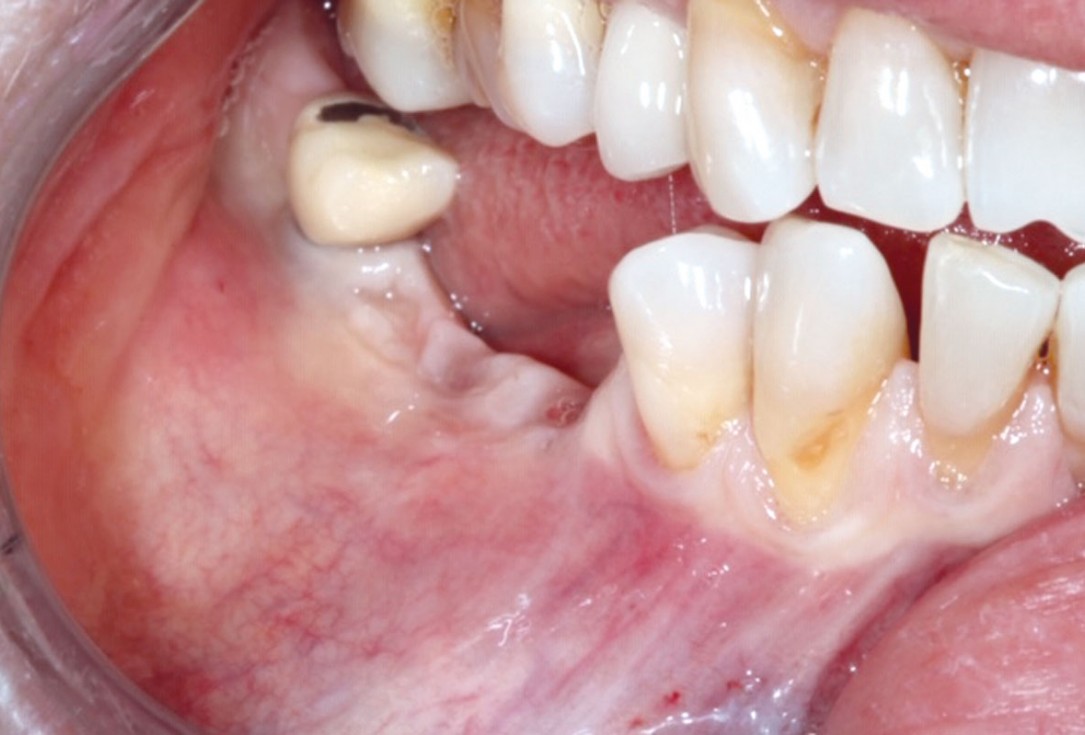

1/10 - Initial clinical situation.GBR with cerabone® and Jason® membrane DentalPro - Dr. A. Gargiulo

Initial clinical situation.